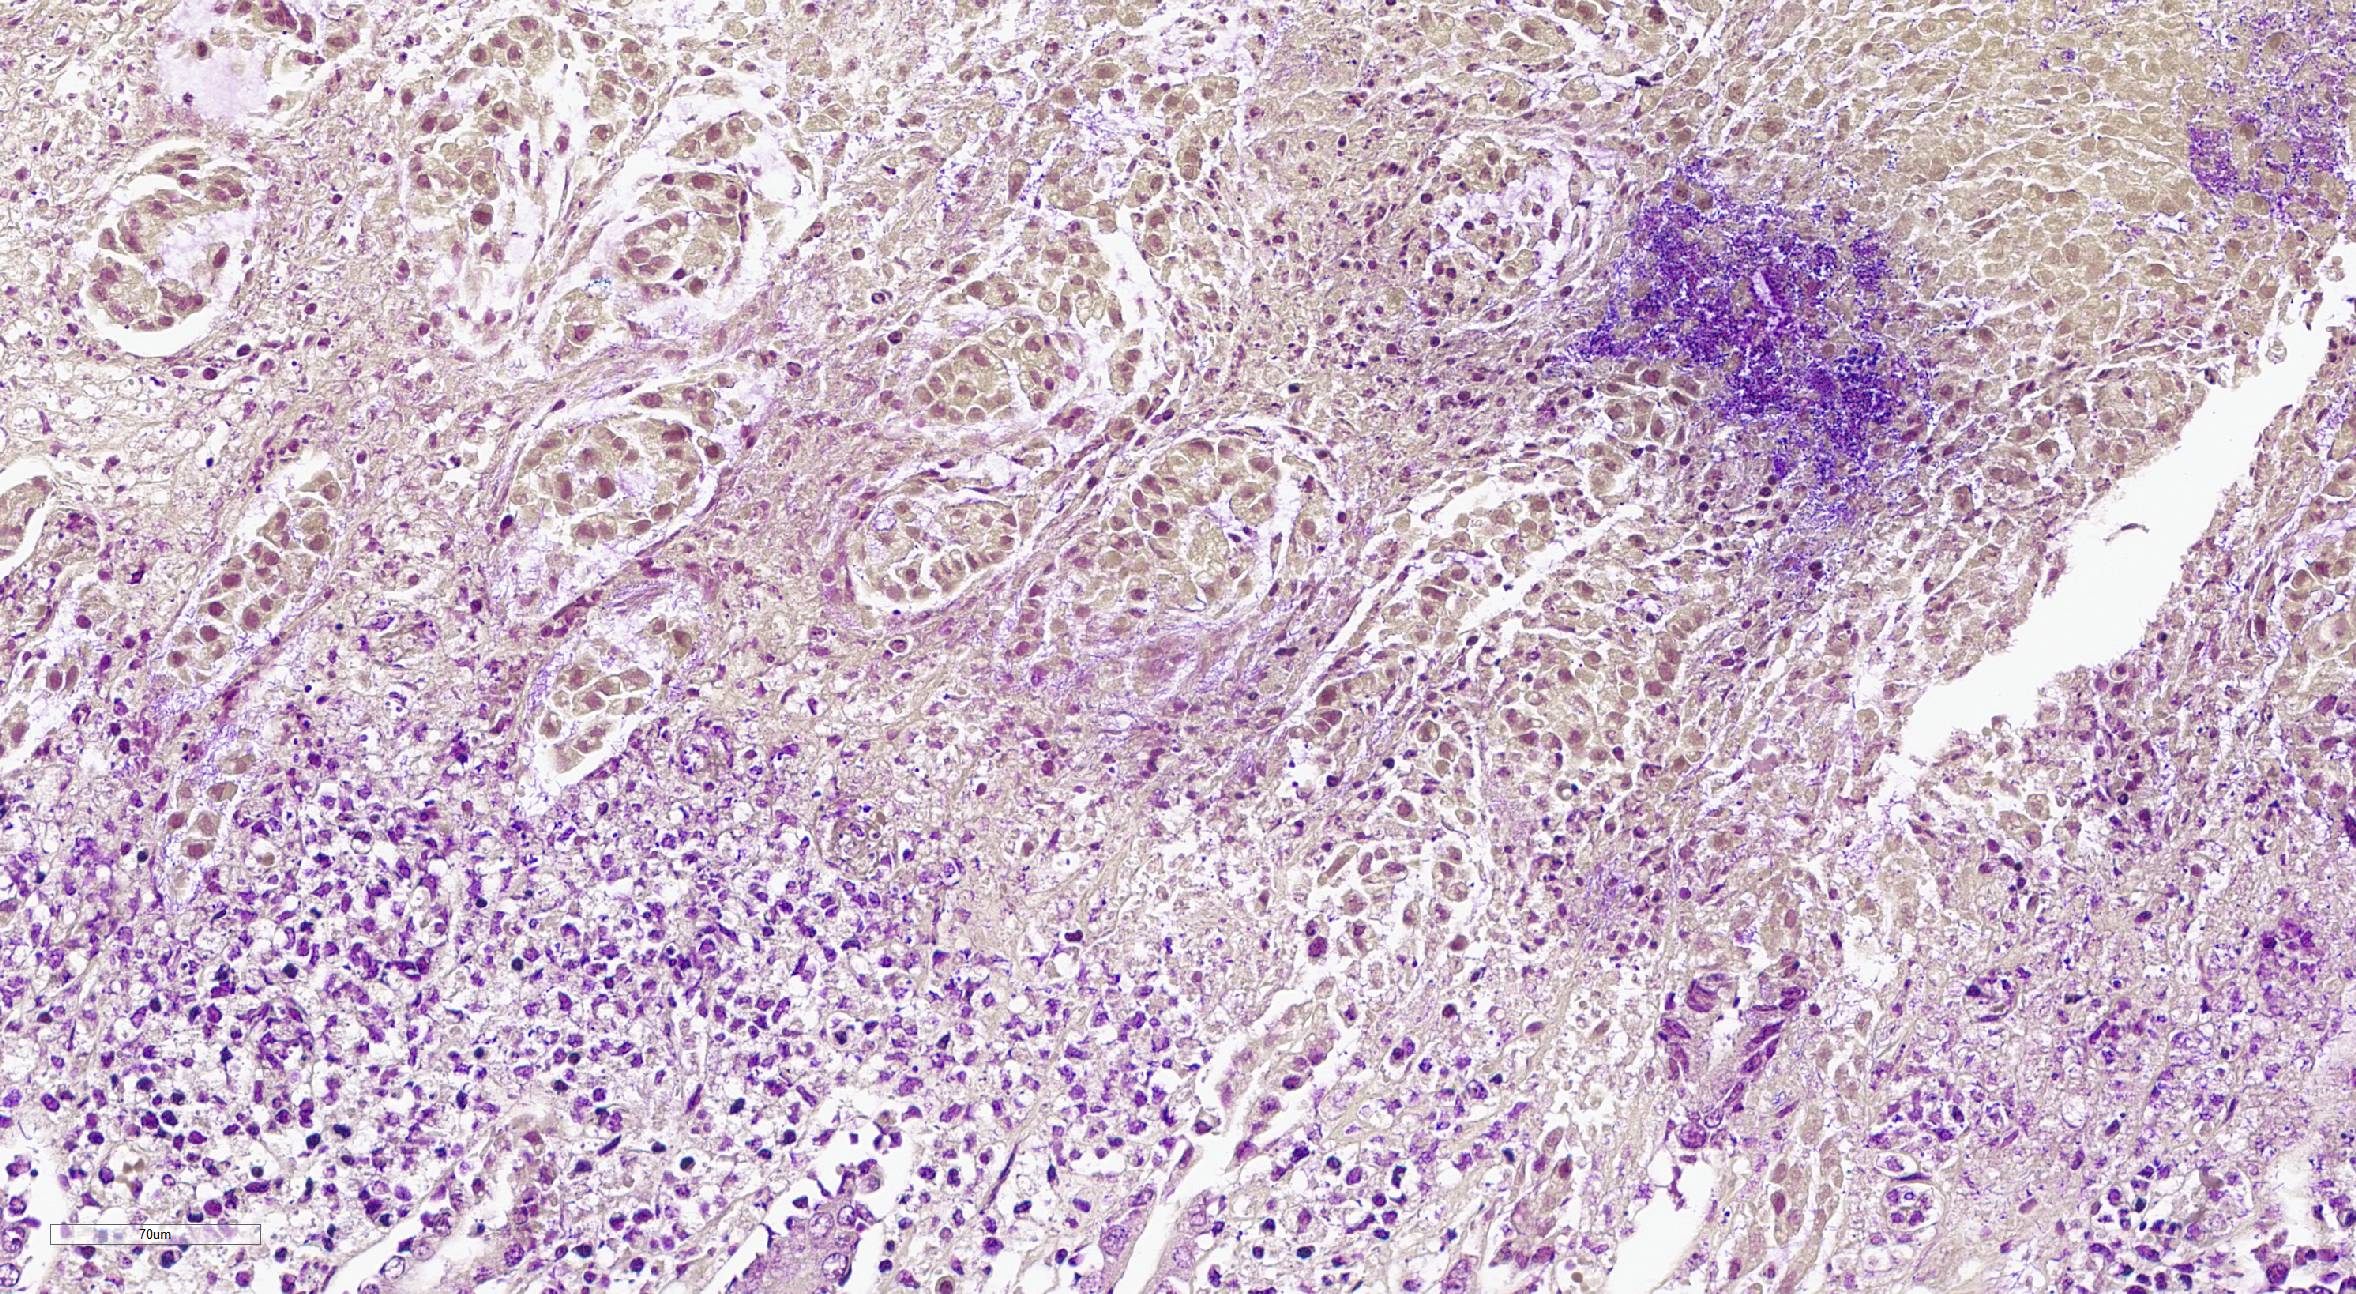

Mandibular lymph node: Lymphoid follicles are indistinct as a result of a severe lymphocyte depletion and replacement by aggregates of epithelioid macrophages with abundant eosinophilic cytoplasm.

Immunohistochemistry examination: Immunohistochemistry using an antibody directed against PCV-2 antigen revealed positive labeling in the cytoplasm of the epithelioid macrophages.

Mandibular lymph node: granulomatous lymphadenitis, mild, multifocal, with lymphoid depletion

There was discussion on the difference between lymphoid necrosis and lymphoid depletion, the former of which implies active targeting of lymphocytes while the latter can be an aftermath of lymphoid necrosis or can be a separate process secondary to any number of pathogeneses (i.e. SCID). The target cell for porcine circovirus-2 is macrophages, and a classic case of PCV-2 may result in granulomatous lymphadenitis, an unusual result of most viral infections. Lymphocytes are not directly targeted in the pathogenesis of PCV-2 but are rather secondary victims to the inflammation from immune response to the virus, making this case a great example of lymphoid depletion. This is further exacerbated in cases of secondary bacterial infection when the offending bacteria colonize Peyer?s patches, which is an important step in the pathogenesis of enteric salmonellosis.

Porcine circovirus-2 is a bit of a catch-all virus in that it causes a wide variety of clinical signs in affected pigs. It should always be on the differential list for sick pigs due to the many ways it manifests. PCV-2 is widely distributed in domestic pigs and wild boars, and has also been isolated from cattle, dogs, deer, chamois, mice, and various arthropods (i.e., ticks and mosquitoes). PCV-2 infection in swine can be either subclinical or cause numerous forms of illness that are collectively referred to as ?PCV-associated diseases? (PCVAD). These includes post-weaning multisystemic wasting syndrome (PMWS), porcine respiratory disease complex, porcine dermatitis and nephropathy syndrome, and both reproductive and enteric diseases.1 The immunosuppression associated with PCV-2 is characterized by lymphopenia, lymphoid cell (both B and T cell) depletion, and altered cytokine production.1 Because of its immunosuppressive effects, PCV-2 is frequently diagnosed concurrently with various other pathogens, and these combinations often provoke more severe disease together than they would individually, as seen in this case with concurrent salmonellosis.